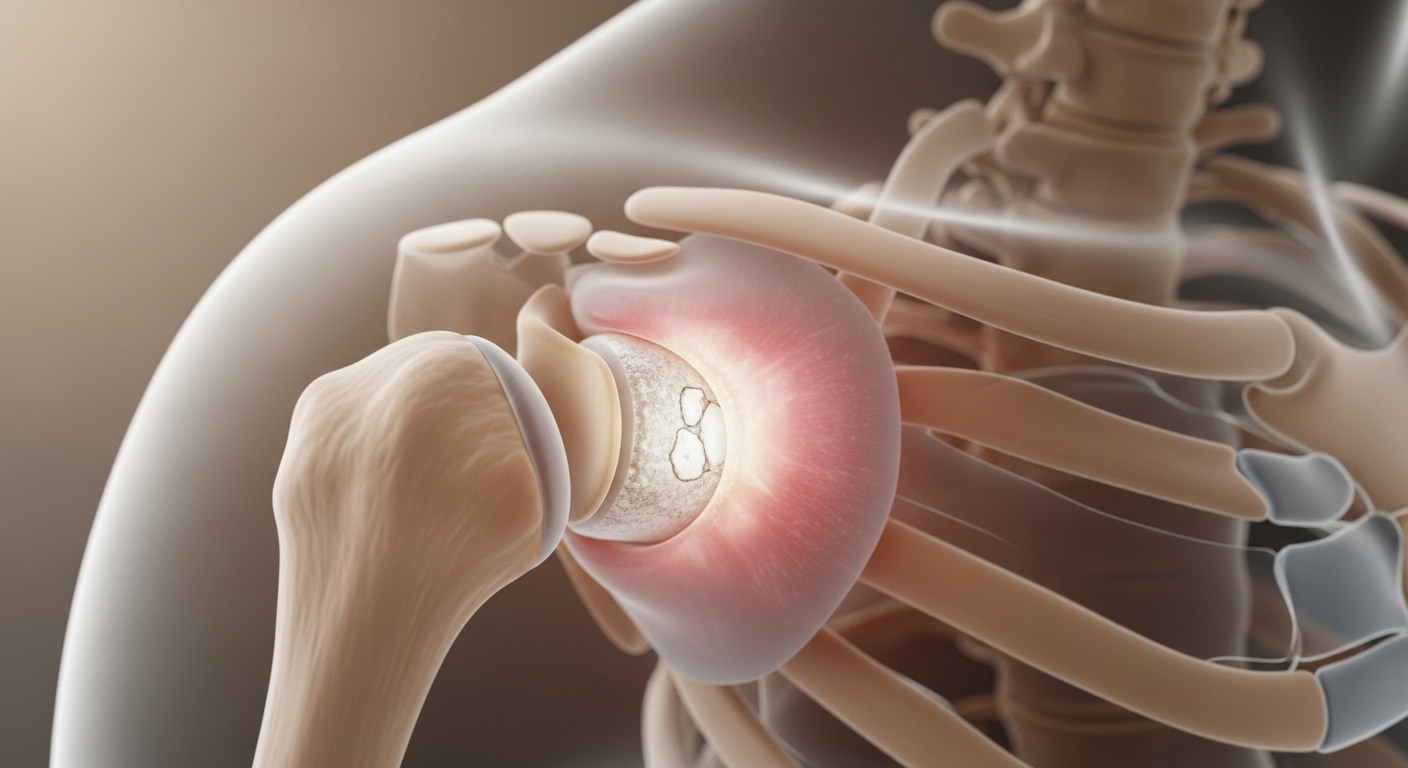

석회성 힘줄염의 가장 특징적인 증상은 뭐니 뭐니 해도 극심한 통증이에요. 특히 통증이 갑자기 시작되는 경우가 많고, 통증 때문에 팔을 움직이는 것이 힘들어집니다. 통증의 시기와 강도에 따라 보통 3단계로 나누어 설명하곤 해요.

- 흡수기 (급성기): 석회가 녹아 흡수되는 과정에서 가장 극심한 통증이 나타납니다. '밤잠을 설치는 통증'이라고 불릴 정도로 매우 아파요.